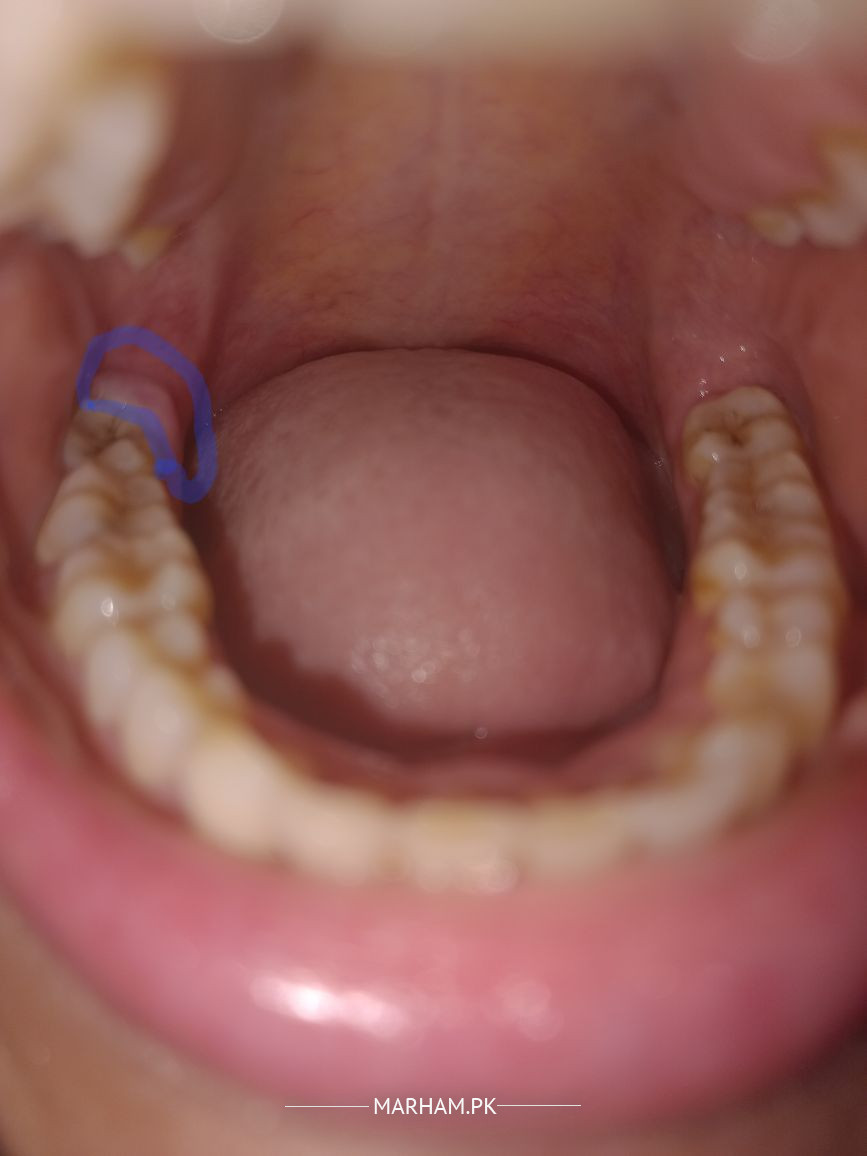

Asking For Self, Female 40, karachi

meray last dahar k bat gum bht swell ho gaya hy 10 days hogey hain bht pain aik face side swelling hogai hai mouthwash bhi kar rahi hu aur 1 side k taraf kha rhi hu per swelling aur pain khatam ni ho raha hy plz koi dawa bata dein

salam ye wisdom tooth(aqal darh) ka pain hai infection dekh rha hai ap xray kerwaye,neem garam pani me rinse kerey

Then it is needed that ypu should go for Extraction. You already are having all prevention. Painkillers and antibiotics will simply decrease the inflammation and delay the extraction.The gum behind your last Wisdom tooth is swelled. Have a proper checkup by a nearby Oral Surgeon.